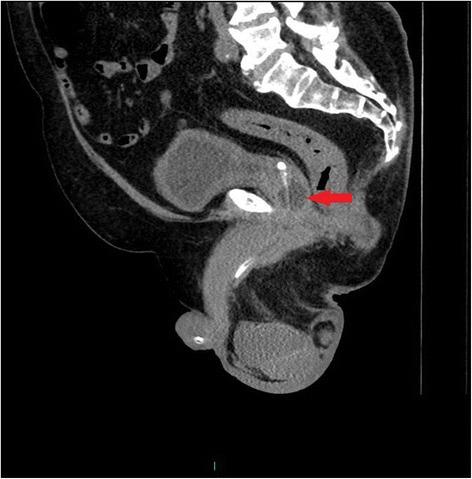

A tetraplegic patient started sweating profusely following insertion of a Foley catheter per urethra. The catheter was draining urine; there was no bypassing, no bleeding per urethra, and no haematuria. Patient's wife, who had been looking after her tetraplegic husband for more than forty years, told the health professionals that the catheter might have been placed incorrectly but her concerns were ignored. Ultrasound scan of urinary tract revealed no urinary calculi, no hydronephrosis. The balloon of Foley catheter was not seen in urinary bladder but this finding was not recognised by radiologist and spinal cord physician. Patient continued to sweat profusely; therefore, CT of pelvis was performed, but there was a delay of ten days. CT revealed the balloon of Foley catheter in the over-stretched prostate-membranous urethra; the tip of catheter was not located within the urinary bladder but was lying distal to bladder neck. Flexible cystoscopy was performed and Foley catheter was inserted into the bladder over a guide wire. The intensity of sweating decreased; noxious stimuli arising from traumatised urethra might take a long while to settle.